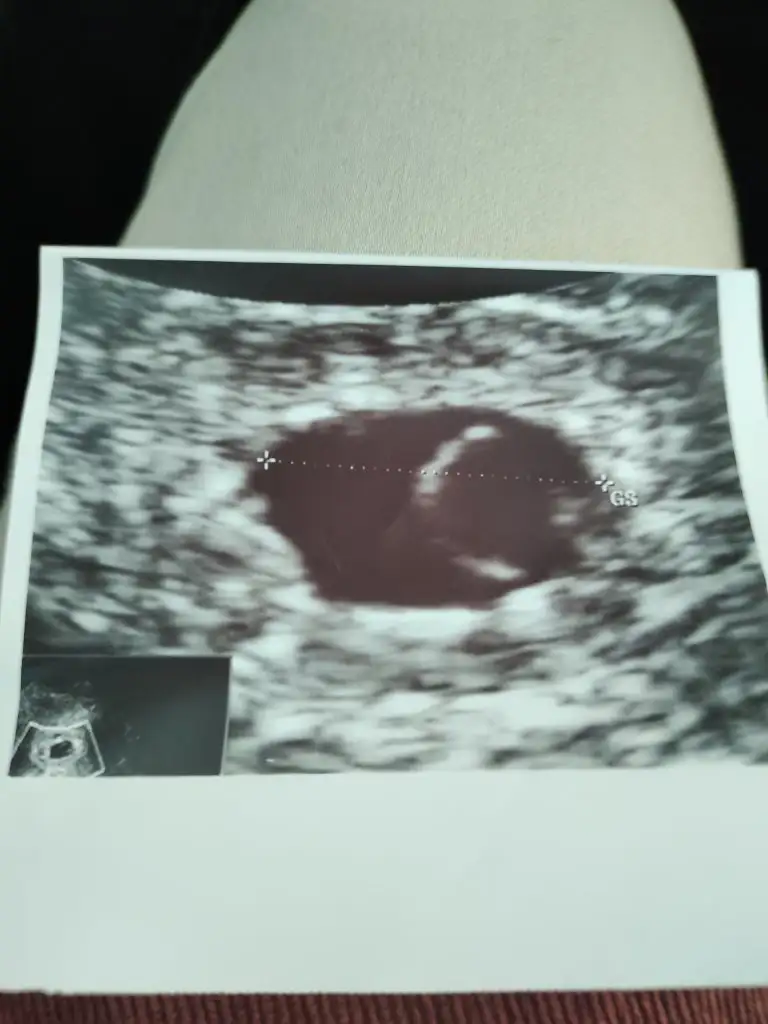

Canım karından bakıldı galiba dimi ondan görülmemiştir bebek haftaya görürsün benceArkadaşlar keseden anlayan varmı yada yazılardan falan doktorum sadece kese var güzel demişti haftaya kalp atışı için gel dedi bende hiç bişey sormadan eve geldim her doktora gitiğimde söyliyeceklerim alkımdam uçup gidiyor sanki 6 hfata denildi bende keseye baktım içinde hiç bebek yok

Valla benim keseyle karşılaştırıp yorumlamaya çalıştım ama olmadı.Bence her şey yolunda çünkü doktor başta bebeği görmedi sonra kalp atışını duyabiliriz dedi. Bana aynen şöyle söyledi kalp atışını duyduk ama duymasaydik bile gayet sağlıklı derdim dedi. Bence bı kaç güne bebek görünür.Arkadaşlar keseden anlayan varmı yada yazılardan falan doktorum sadece kese var güzel demişti haftaya kalp atışı için gel dedi bende hiç bişey sormadan eve geldim her doktora gitiğimde söyliyeceklerim alkımdam uçup gidiyor sanki 6 hfata denildi bende keseye baktım içinde hiç bebek yok

Canım 6 hafta olduğundan emin misinArkadaşlar keseden anlayan varmı yada yazılardan falan doktorum sadece kese var güzel demişti haftaya kalp atışı için gel dedi bende hiç bişey sormadan eve geldim her doktora gitiğimde söyliyeceklerim alkımdam uçup gidiyor sanki 6 hfata denildi bende keseye baktım içinde hiç bebek yok